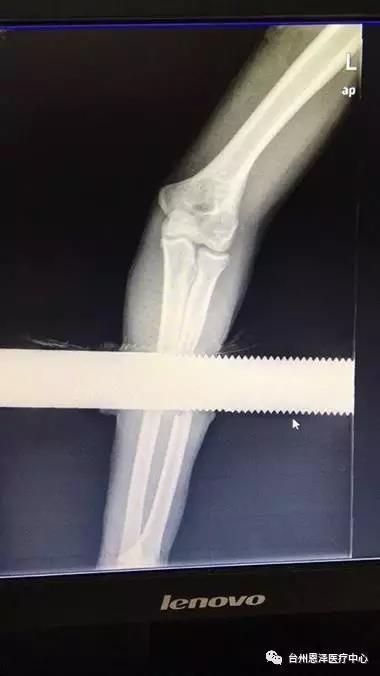

经测量贯穿松平手臂的实心钢棒长1.3米,直径6厘米。

接着沿伤口两侧作纵形切开,充分显露出铁棍周围的肌肉和神经,洪海南医生负责牵开,以免去除棍子时将肌肉与神经卷入,再小心地将棍子及衣服碎片从肌肉里取出来。这样,左前臂中段形成了一个空洞。仔细探查空洞周围组织,发现左桡骨中段已缺损伴周围肌肉的严重损伤,但尺骨是完整的,前臂两大神经(正中神经和尺神经)只是挫伤,连续性存在。

钢棒被一寸一寸地分离出来……经过两个小时的紧张手术,钢棒终于成功取出。医生马上对伤口进行清创处理,切除挫伤污染的皮肤及肌肉组织,咬除桡骨断端污染的骨组织,然后清洗伤口,最后进行伤口缝合,用石膏外固定。